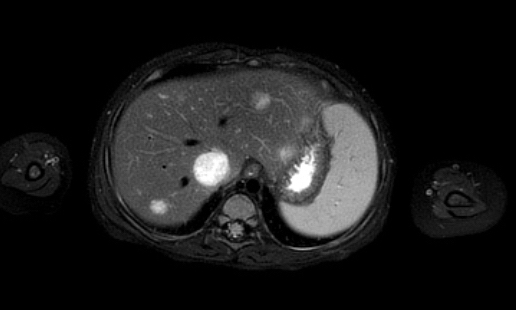

Ví dụ 1

Một bé gái ba tuổi có khối u thận trái và huyết khối khối u lớn trong tĩnh mạch thận và tĩnh mạch chủ dưới. Có di căn gan (phát hiện không thường gặp) và di căn phổi.

Lưu ý huyết khối u trong tĩnh mạch thận trái kéo dài vào tĩnh mạch chủ dưới.